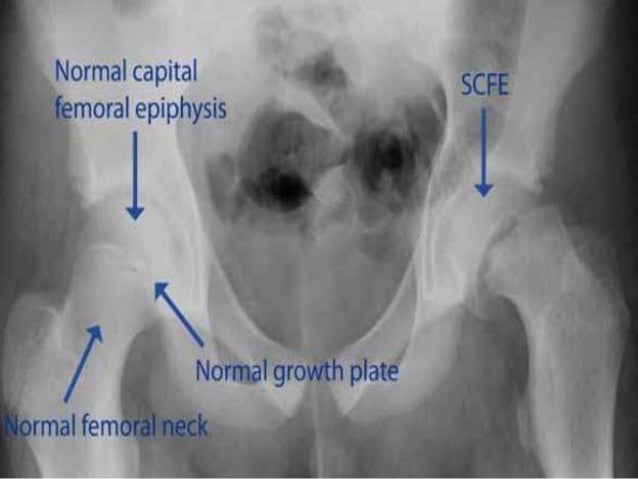

Slipped Capital Femoral Epiphysis | UW Emergency Radiology

faculty.washington.edu

faculty.washington.edu

femoral epiphysis slipped capital radiology scfe hip normal